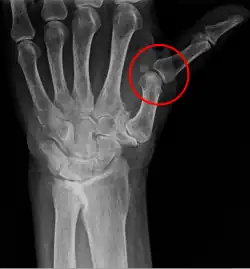

X-ray showing metacarpophalangeal subluxation of the thumb of a 71-year-old woman due to trapeziometacarpal osteoarthritis

A subluxation of a joint is where a connecting bone is partially out of the joint.[5] In contrast to a luxation, which is a complete separation of the joint, a subluxation often returns to its normal position without additional help from a health professional.[6] An example of a joint subluxation is a nursemaid's elbow, which is the subluxation of the head of the radius from the annular ligament. Other joints that are prone to subluxations are the shoulders, fingers, kneecaps, ribs, wrists, ankles, and hips affected by hip dysplasia. A spinal subluxation is visible on X-rays and can sometimes impinge on spinal nerve roots, causing symptoms in the areas served by those roots. In the spine, such a displacement may be caused by a fracture, spondylolisthesis, rheumatoid arthritis,[7] severe osteoarthritis, falls, accidents and other traumas.